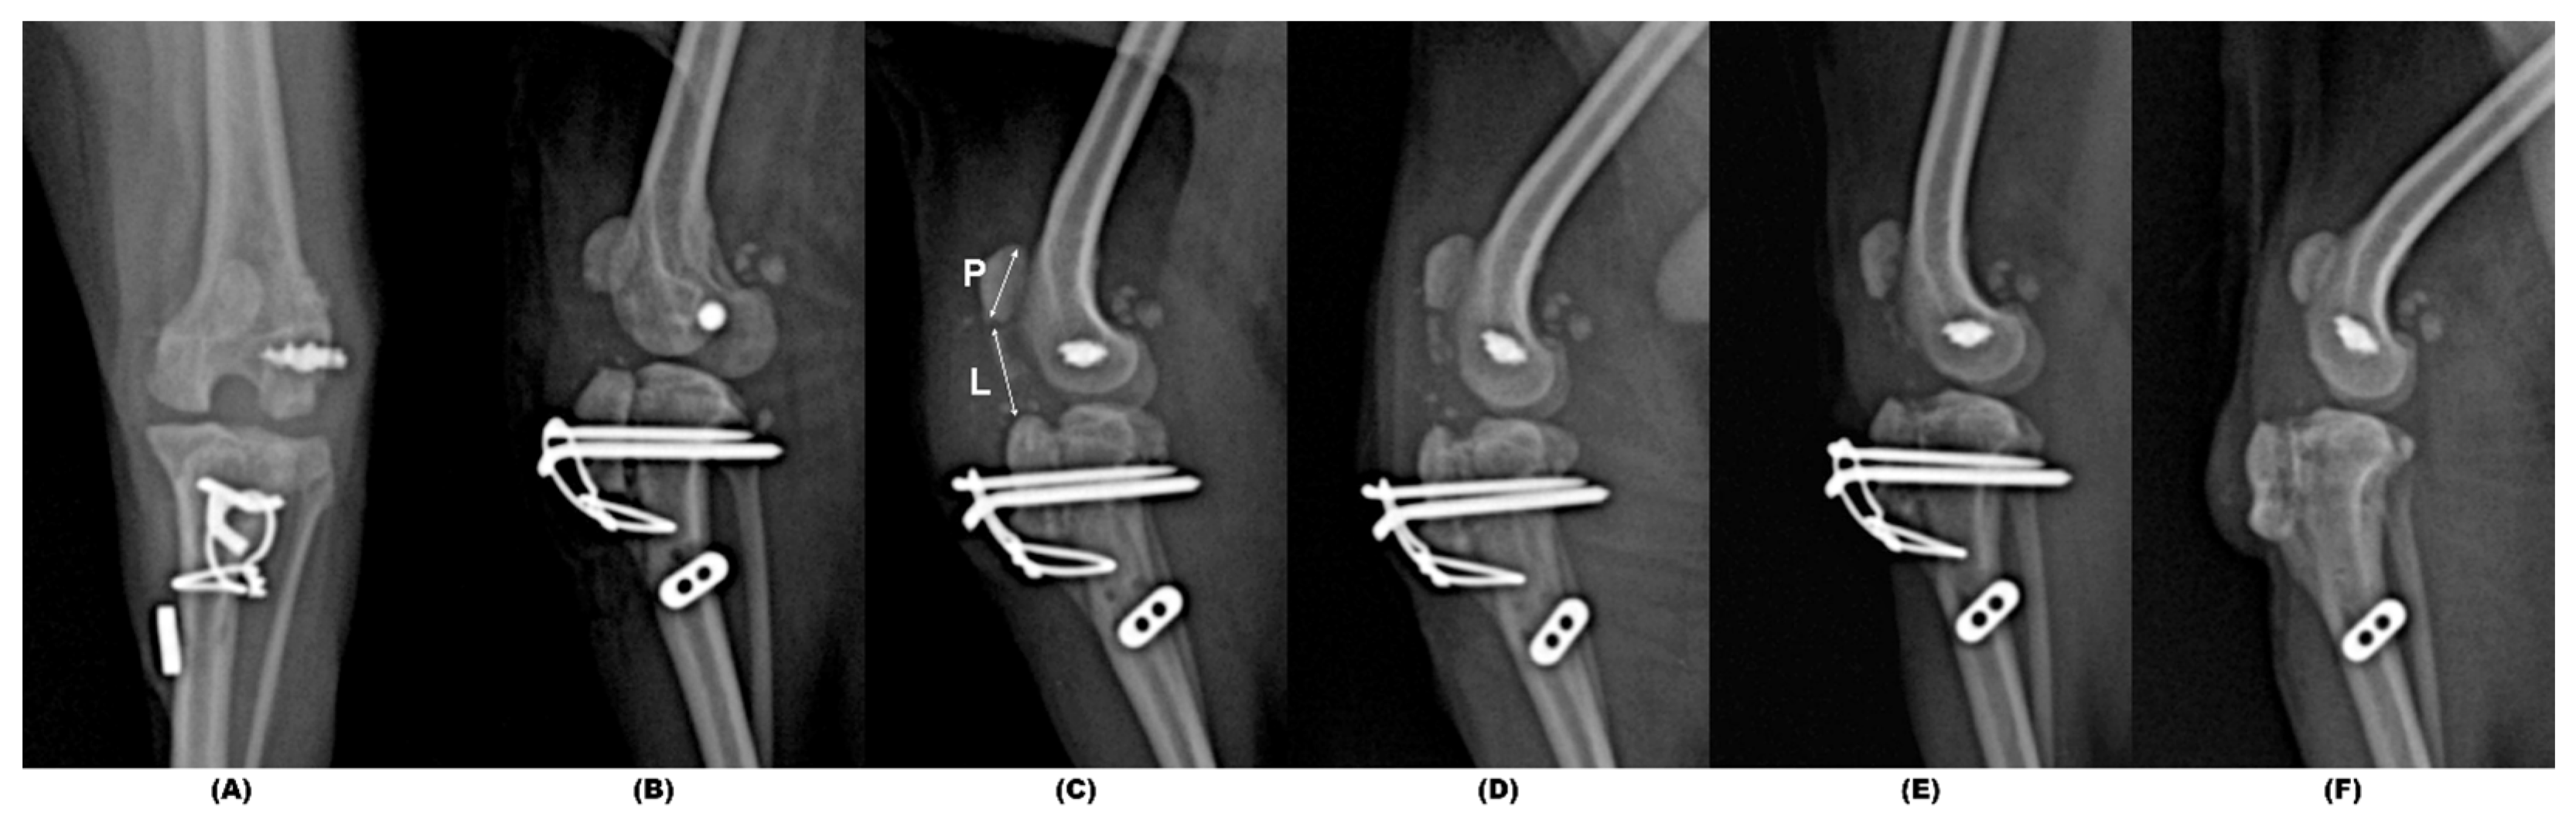

2. Case Description